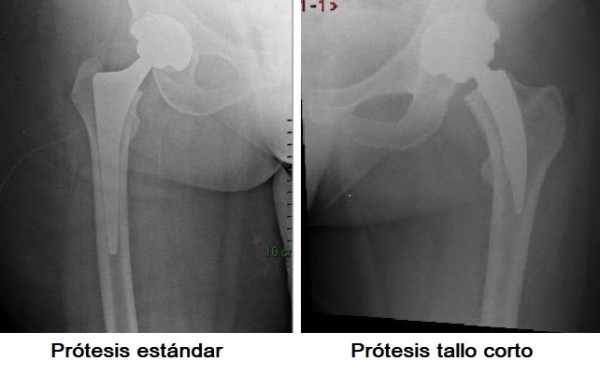

Con respecto a la prótesis, en Argentina comúnmente se usa una prótesis estándar que se coloca dentro del hueso del fémur, se trabaja en la parte central del hueso con raspas especiales. “La prótesis estándar es excelente, sin embargo la nueva que estamos usando es más chica e invade menos hueso. En donde innovamos es en hacer la combinación del abordaje anterior con la prótesis corta, cosa que no se había hecho en Argentina. Logramos un abordaje chico, poco doloroso, sin cortar músculo, invadiendo poco hueso, el paciente puede caminar al otro día y se puede ir a la casa. La diferencia es extrema”.

La principal ventaja de la prótesis de talle corto es que la cirugía mínimamente invasiva. «Se invade menos hueso, esto es muy importante porque las prótesis duran entre 15 y 20 años y luego hay que volver a operar y se pasa a utilizar una prótesis más larga, entonces hay que invadir más hueso para lograr mayor fijación. Si comenzamos usando la más corta, le ganamos años de vida al hueso del paciente», explicó López.